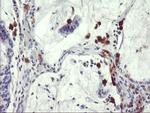

SDS Antibody in Immunohistochemistry (Paraffin) (IHC (P))

SDS Antibody (CF503997) in IHC (P)

Immunohistochemical staining of paraffin-embedded Adenocarcinoma of Human colon tissue using anti-SDS mouse monoclonal antibody. (Heat-induced epitope retrieval by 10mM citric buffer, pH6.0, 100°C for 10min, TA503997) {{ $ctrl.currentElement.advancedVerification.fullName }} 验证信息 View more